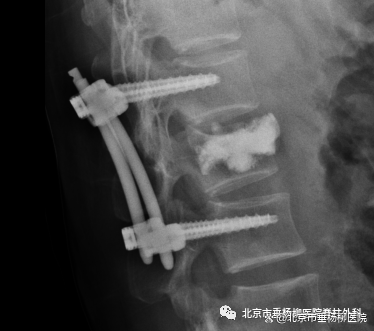

因为此类患者群体普遍具有年龄大、基础病多、骨强度显著下降、伤椎椎体压缩严重、骨折局部后凸畸形,特别是椎体后壁破损不完整等特点,使得手术治疗过程中极易产生问题。随着相关医疗研究的推动,以及机器人手术技术的普及,在临床治疗过程中,医生通过机器人手术来提高手术精准度,减少手术创伤及术中放射性损害,显著提高了手术成功率。为最大程度减少手术创伤,同时减轻患者身心和经济负担,解决医护人员在手术中射线辐射问题,提高手术精准度,医院骨四科(脊柱外科)于2019年引入“天玑”骨科机器人。骨科机器人辅助技术可以在手术中进行辅助经皮椎弓根螺钉固定联合伤椎PKP技术,精准治疗椎体爆裂骨折。

在治疗中,术前首先使用三维C形臂对患者的骨折部位完成一次低剂量辐射的三维X线扫描(用时仅45秒,根据检测该扫描过程的X线辐射剂量仅相当于一次普通胸片检查的辐射剂量),再将所获得的连续扫描影像数据传输到机器人的电脑平台,然后由术者使用机器人电脑操控进行经皮穿刺路径的模拟规划,操作熟练的手术医生一般在5分钟内便可完成6条近乎完美的穿刺路径规划。最后,在机器人红外相机导航下引导机器人手臂自动游弋定位至前期规划好的穿刺点及穿刺方向,插入导向套筒后手术医生可以一次性精准安全地将导针经皮钻入椎弓根至椎体内,避免了反复调整过程,相同操作再依次完成其它所有导针的置入。后续的空心螺钉植入和PKP操作便可在少数X线透视下轻松顺利完成,整体手术时间明显缩短,且X线辐射损伤风险也显著降低,最终伤口仅需4针缝线。